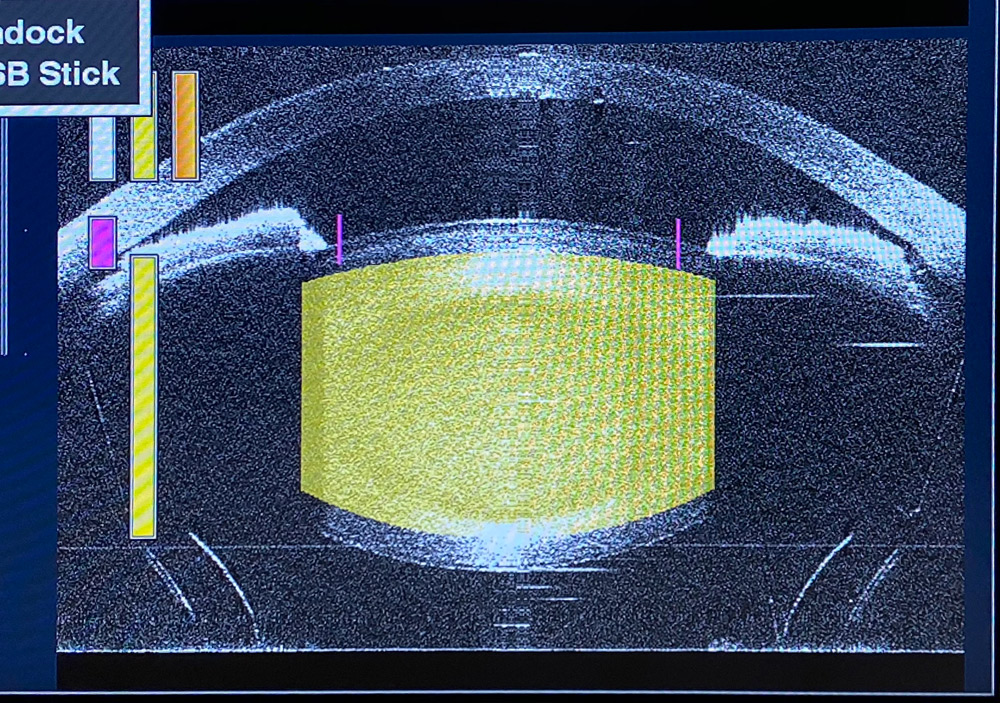

Doing FLACS in these cases, Dr. Noecker said, softens the nucleus so there is less energy being used in a small workspace, and the nucleus can be removed with less manipulation as well, which has advantages in preserving the corneal endothelium and the structures of the angle.

In general, Dr. Noecker said glaucoma patients tend to have other comorbidities and anterior segment disease, whether corneal or in the angle, and using FLACS can be an advantage. For example, in cases of pseudoexfoliation lenses with weak zonules, FLACS can reduce lens manipulation and can provide a complete capsulorhexis with minimal stress on the zonules. In addition, since these patients tend not to have large pupils, the capsulorhexis can be at the pupil margin for maximal sizing without worry of extension underneath the pupil when it might otherwise be difficult.